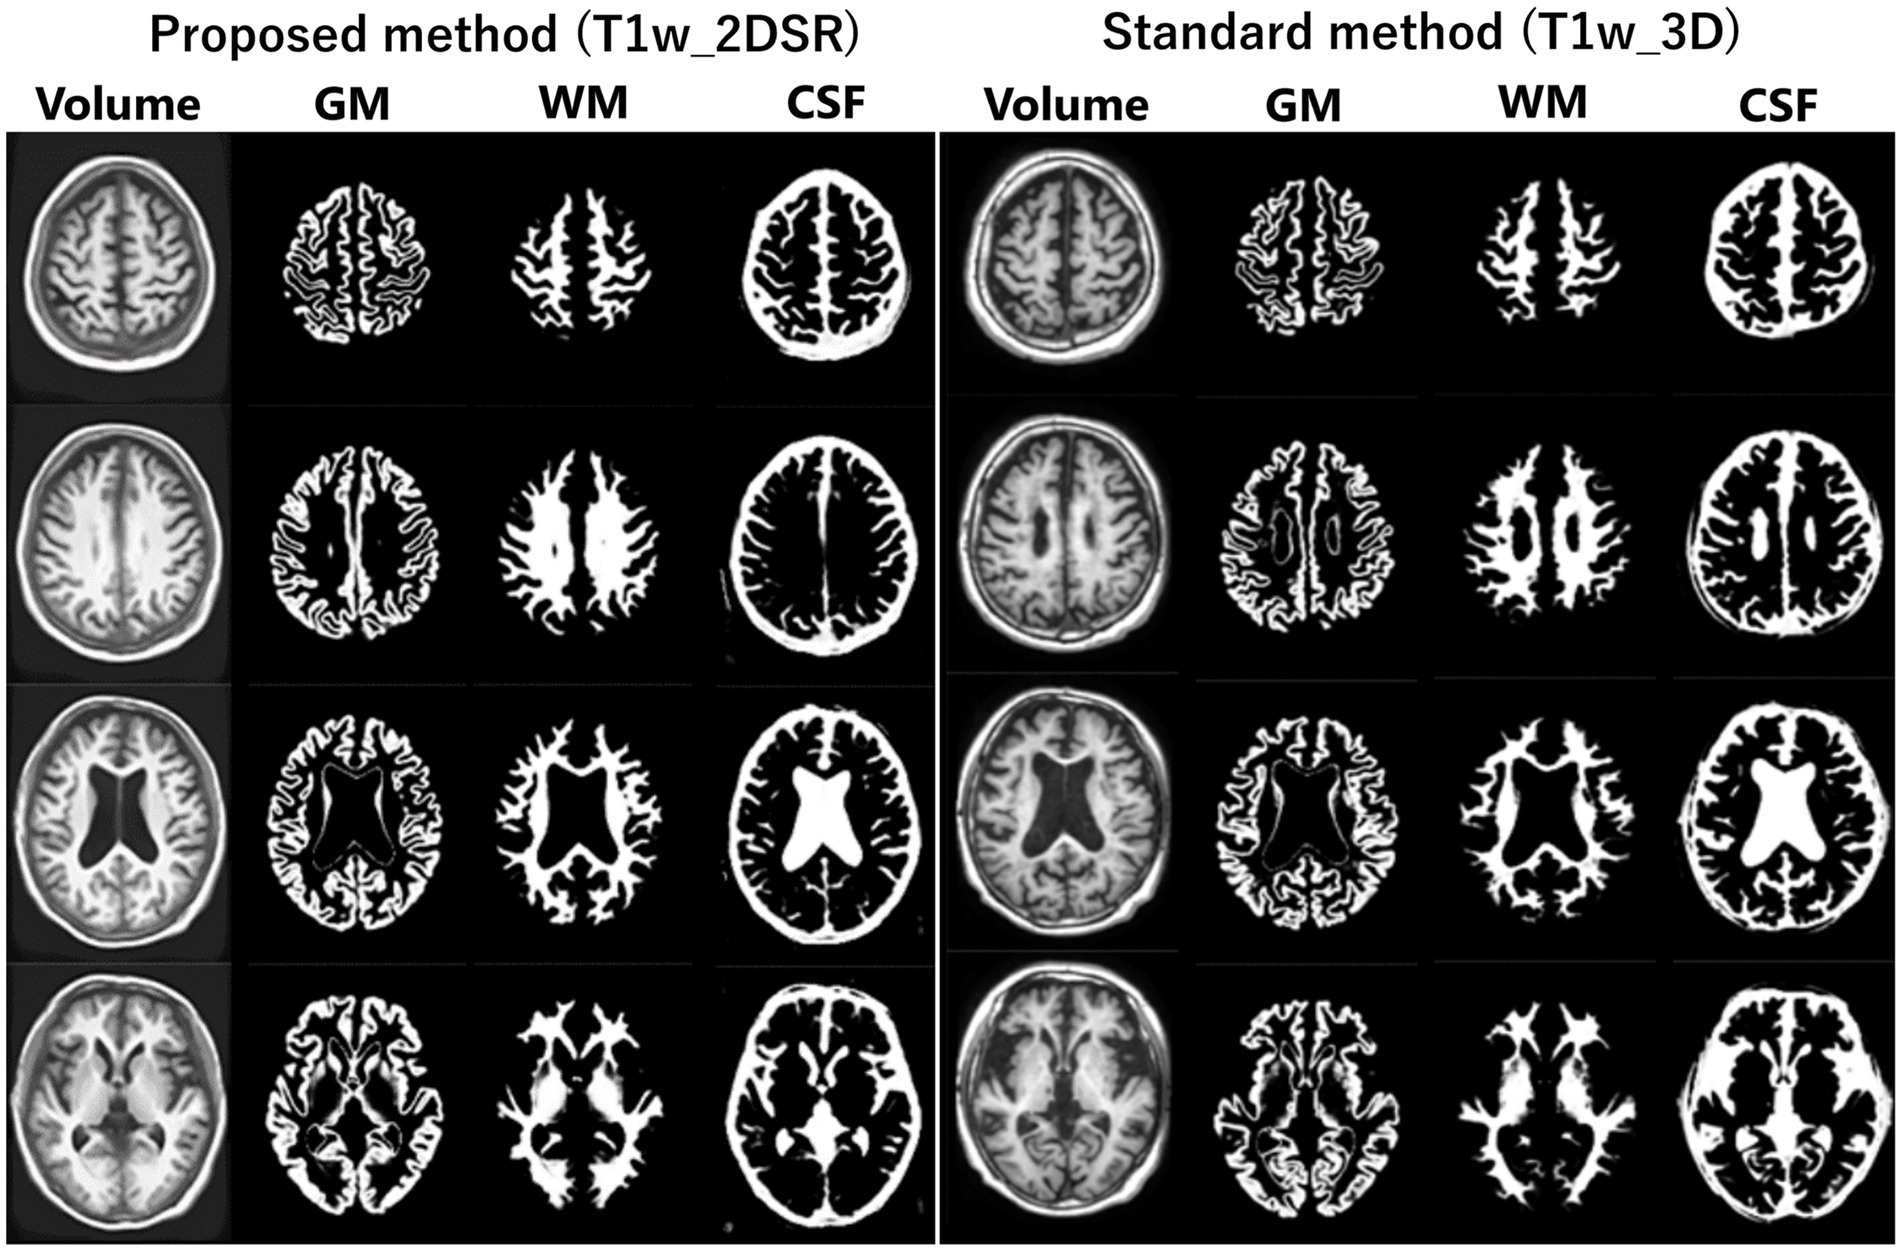

Several versions of VSRAD have been developed. In this study, we used “VSRAD advance,” which was based on SPM 8 and incorporated DARTEL (11, 22, 23). VBM was performed on both T1w_2DSR and T1w_3D, yielding data on segmented white matter (WM), gray matter (GM), CSF (Figure 2). Four Z-scores reflecting the degree of atrophy in the specific volume of interest (VOI) were automatically calculated and provided by VSRAD advance, based on comparing each patient’s data with an internal database of 80 healthy volunteers. The Z-score was defined as [(control mean) – (individual value)]/(control standard deviation) (11). The Z-scores generated by VSRAD advance visualize and quantitatively evaluate the degree of gray matter atrophy in the regions of interest, primarily the parahippocampal gyrus including the medial temporal lobe, which is closely associated with Alzheimer’s disease, by measuring the degree of deviation from the normative brain database. The four scores were as follows: Score 1 “Severity”: Z-score reflecting the severity of GM atrophy in the VOI. Score 2 “Extent”: the extent of GM atrophy in the VOI. Score 3 “Ratio”: the ratio of the extent of GM atrophy in the VOI to the whole brain. Score 4 “Maximum”: the maximum z-score of the severity of GM atrophy in the VOI of AD (24–28). To mitigate volumetric inaccuracies introduced by non-linear spatial normalization and Gaussian smoothing in the DARTEL pipeline, intermediate WM and GM segmentation files were used for estimating native-space volumes. Total brain volume was calculated as the sum of the WM and GM volumes (WM + GM). Measurements were performed using the Segment Statistics module of 3D Slicer (13).

Figure 2. Segmented images obtained by VSRAD. The left panel shows the VSRAD analysis results using the SynthSR-based method (T1w_2DSR). Segmented gray matter (GM), white matter (WM), cerebrospinal fluid (CSF) images were successfully generated. The right panel shows the comparison of segmented GM, WM and CSF images using the standard method (T1w_3D). These results indicate that the volume data generated by SynthSR demonstrated comparable segmentation performance to 3D data from standard methods.